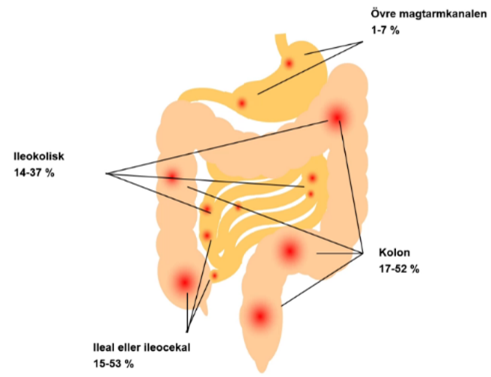

Crohns sjukdom, geografi och utbredning?

- Kan drabba hela GO från mun –> anus men mest i ileum och kolon (mkt bakterier)

- Transmural inflammation

- Skipped lesions

- Inflammation –> stenos –> perforation

Ulcerös kolit, geografi och utbredning?

- Börjar distalt i rektum och breder ut sig proximalt

- Endast kolon

- Mukosal inflammation (bara slemhinna)

- Kontinuerlig inflammation

- Vänstersidig kolit (rektum, sigmoideum och vänster flexur)

- Rektum

- Bortom vänster flexur – extensiv/total kolit